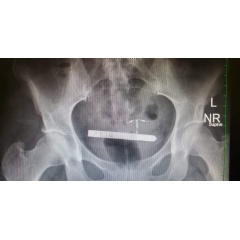

Surgeons at The Marchand Institute for Minimally Invasive Surgery have removed the device from a patient’s bladder already using a cystoscopic approach.

Making matters worse, health professionals do not routinely search the bladder for foreign bodies, as it is unusual for a large object to enter the bladder because of the narrow opening of the urethra. Therefore the device could be difficult to locate by radiology or surgical exploration. It is much more common for an object to penetrate the posterior wall of the vagina and enter the abdominal cavity, or to be unretrievable in the rectum. Therefore location and removal of these devices can be difficult and could lead to unnecessary extra surgery or complications.